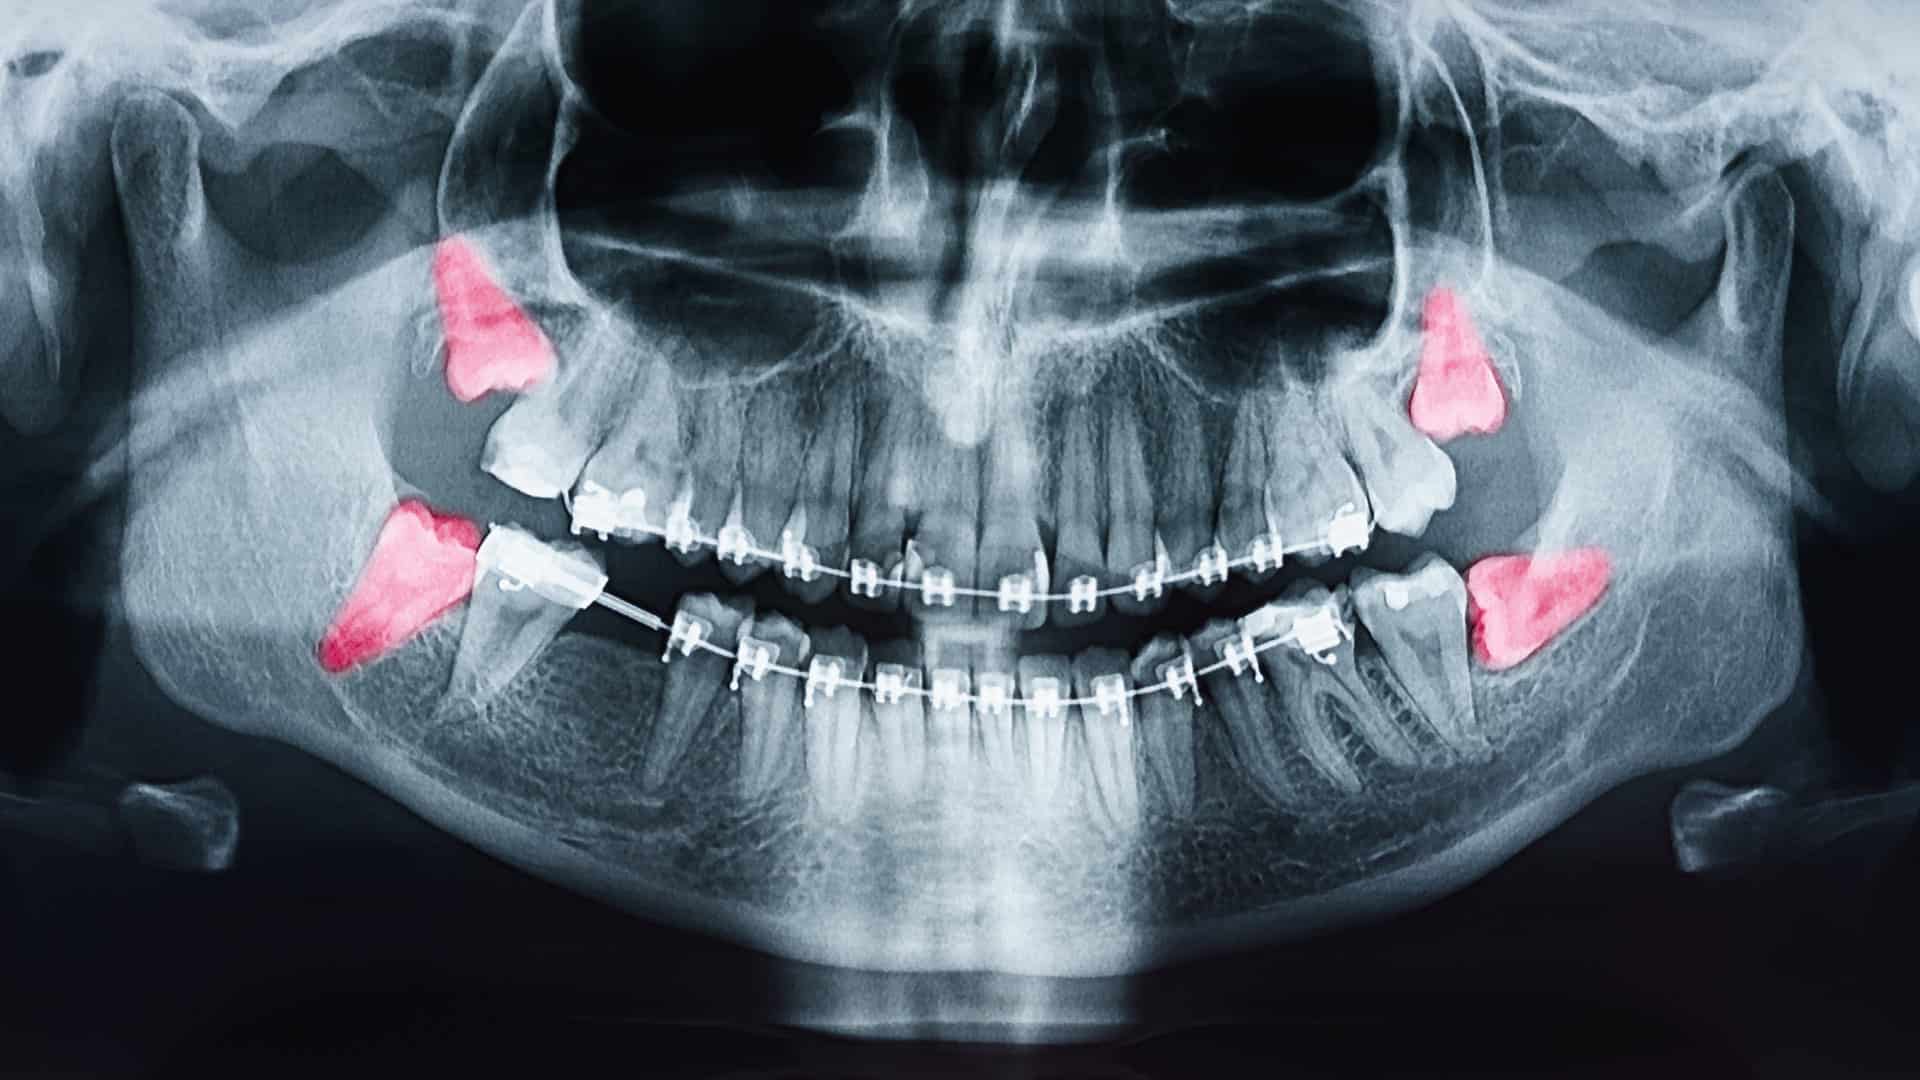

- Avaliação clínica e radiográfica: O dentista ou cirurgião bucomaxilofacial realiza exames clínicos e radiográficos (como a radiografia panorâmica), avaliando a posição, angulação e desenvolvimento dos sisos para indicar o momento certo de extração (American Association of Oral and Maxillofacial Surgeons [AAOMS], 2020).

- Radiografia panorâmica: Exames de imagem são essenciais para planejar o acompanhamento e avaliar a angulação dos terceiros molares.